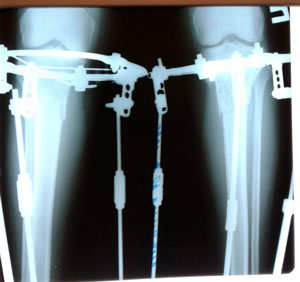

Дата операции - 15.07.2019г.

Дата снятия аппаратов - 15.10.2019г.

Срок сращения 90 дней.